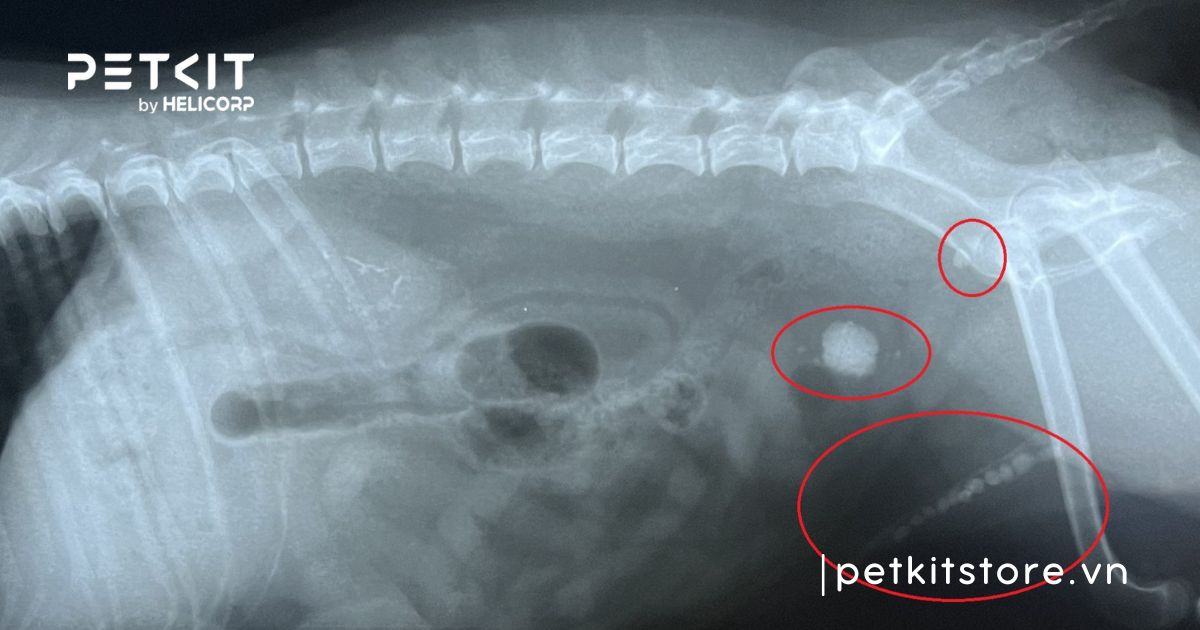

- Chụp X-quang: Hỗ trợ trong việc phát hiện các loại sỏi bàng quang hoặc bất thường khác.

2.2 Sỏi bàng quang

Sỏi đường tiết niệu hay sỏi bàng quang có thể dẫn đến tình trạng xuất hiện máu trong nước tiểu của mèo, gây ra các vấn đề sức khỏe đáng lo ngại. Các tinh thể khoáng chất như canxi oxalat hoặc struvite có thể tích tụ và hình thành sỏi trong bàng quang làm tắt niệu đạo. Từ đó gây ra tình trạng nhiễm trùng đường tiết niệu, khó tiểu và tiểu ra máu ở mèo.

Sỏi đường tiết niệu hay sỏi bàng quang có thể khiếm mèo tiểu ra máu